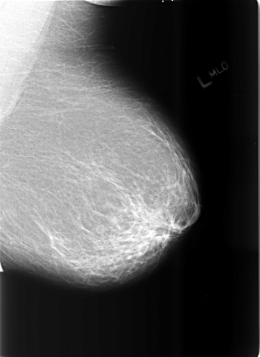

ics_version 1.0 filename B-3465-1 DATE_OF_STUDY 12 5 1998 PATIENT_AGE 67 FILM FILM_TYPE REGULAR DENSITY 2 DATE_DIGITIZED 7 4 1999 DIGITIZER LUMISYS LASER SEQUENCE LEFT_CC LINES 5680 PIXELS_PER_LINE 4176 BITS_PER_PIXEL 12 RESOLUTION 50 NON_OVERLAY LEFT_MLO LINES 5704 PIXELS_PER_LINE 4152 BITS_PER_PIXEL 12 RESOLUTION 50 NON_OVERLAY RIGHT_CC LINES 5696 PIXELS_PER_LINE 4088 BITS_PER_PIXEL 12 RESOLUTION 50 OVERLAY RIGHT_MLO LINES 5712 PIXELS_PER_LINE 4104 BITS_PER_PIXEL 12 RESOLUTION 50 OVERLAY |